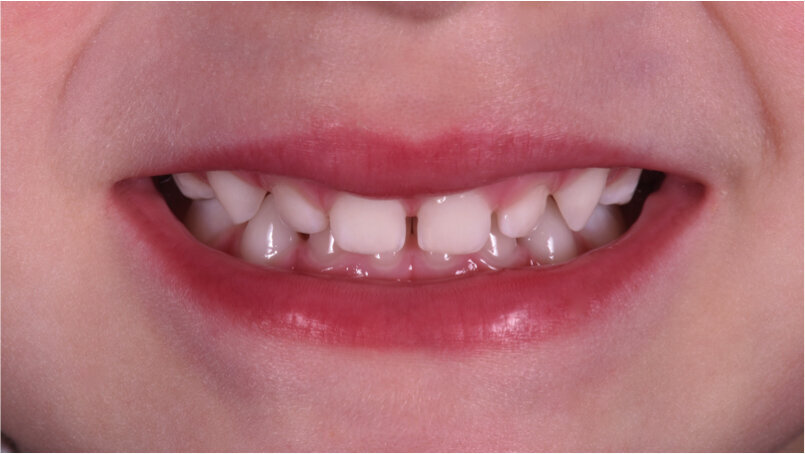

Caso 2 Paziente di anni 4, malocclusione dentale di III Classe, morso crociato monolaterale dx. La paziente viene trattata con dispositivo Amcop TC 2, il quale indossato tutte le notti e 1 ora di pomeriggio in 8 mesi risolve la malocclusione ripristinando il corretto rapporto occlusale; durante la terapia si riscontra un netto miglioramento della respirazione nasale e quindi il ripristino delle normali funzioni respiratorie. Il dispositivo, nei mesi successivi, viene indossato dalla paziente solo la notte per stabilizzare il caso e per guidare la crescita nel miglior modo possibile; all’età di 6 anni la paziente viene sottoposta a check-up ortodontico completo e quindi a panoramica e teleradiografia per poter analizzare anche la previsione di crescita e stabilire un eventuale step elastodontico (Figg. 15-23).

Caso 3 M.D.E Anni 2, succhiamento protratto del dito, deglutizione atipica, open bite dentale, contrazione arcata superiore. I genitori riferiscono difficoltà a respirare e raffreddori ricorrenti (Figg. 24-28).